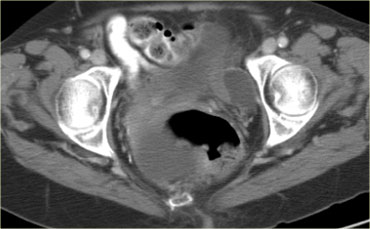

CT của cùng bệnh nhân xác nhận các tổn thương đặc-nang phức tạp hai bên kích thước lớn, phồng vào ổ bụng.

Mục đích của CT không phải là xác nhận những gì đã biết từ siêu âm, mà là để phân giai đoạn bệnh.

Dựa trên CT (hoặc MRI), không thể xác định loại mô học của khối u.

Điều này không có ý nghĩa quyết định. Bệnh nhân này sẽ được phẫu thuật.

Đối với các u biểu mô – nhóm u ác tính buồng trứng thường gặp nhất – ngay cả sau phẫu thuật, phân loại mô học chính xác của khối u ít quan trọng hơn nhiều đối với tiên lượng so với các yếu tố như giai đoạn FIGO, độ biệt hóa khối u và mức độ thành công của phẫu thuật trong việc loại bỏ toàn bộ bệnh.

Đối với bệnh nhân này, các đặc điểm quan trọng được thể hiện trên hình bên trái.

Có một tổn thương cấy ghép phúc mạc.

Khối u đã được phẫu thuật cắt bỏ và kết quả giải phẫu bệnh cho thấy đây là ung thư biểu mô buồng trứng dạng nội mạc tử cung.